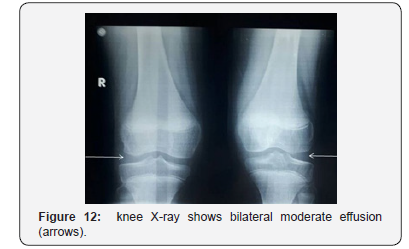

Laboratory tests revealed normal ranges of CBC, ESR, CRP, Albumin, Creatinine, Urea, electrolytes. Anti-CCP, RF, ANAwere all negative. Cardiac ultrasound showed no effusion. Knee ultrasound showed bilateral moderate effusion. Plain radiograph of both hands showed flexion at the 4th and 5th distal interphalangeal (DIP) joints of the right hand (Figure 11). Knees X-ray (Figure 12) and pelvis anterior-posterior radiograph (Figure 13) showed similar findings to her younger sister. Knees MRI revealed a mild increased in soft tissue, moderate bilateral joint effusion and intraosseous filled-fluid herniation (Figure 14). Hip MRI showed moderate effusion and susceptible intraosseous cysts without erosions (Figure 15). She was discharged along with acetaminophen (15 mg/k) with the possibility of surgery if severe symptoms have developed..

Radiological appearances confirm the diagnosis of CACP. Knees X-ray showed osteopenia, bilateral effusion, swelling of soft tissues, joint space widening, and epiphyseal widening of both knees. Knee MRI image of the older sister, patient 2, showed intraosseous cysts inside the bone, without bone erosion [12].